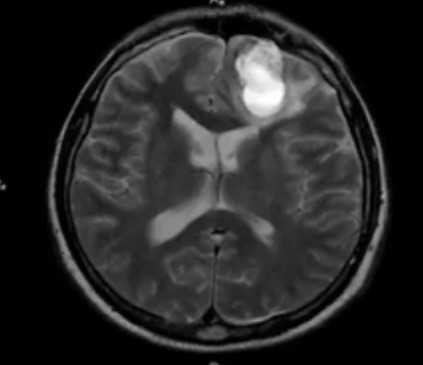

Расшифровка томографии черепа

Внутримозговая гематома травматического характера на МР-снимке

В результате МРТ получают множество послойных снимков в трех взаимно-перпендикулярных плоскостях. На изображениях видят контуры тканей, сравнивают показатели с нормой, выявляют отклонения и признаки патологических изменений. Все данные отражают в заключении.